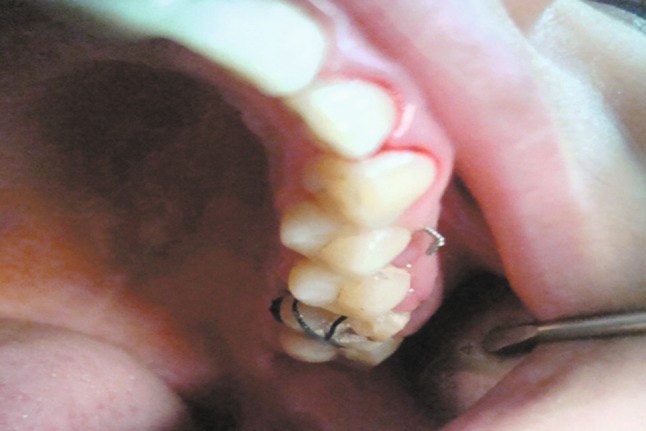

Fig. 3.

Maintaining the third molar into the new socket